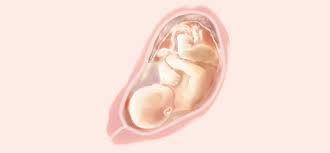

Sus pulmones ya pueden funcionar en el exterior. Escrito por Jade Magdaleno matrona. O seu bebê está com cerca de 40cm e 2kg o desenvolvimento está quase completo. Hola chicas espero esten super bien. Aprende todo lo relacionado con el desarrollo de tu bebé y los cambios en tu cuerpo a las 34 semanas de embarazo. El cuerpo se está preparando para el parto. 232 a 238 dias de gestação Na 34ª semana de gestação os pulmões do bebê já estão completamente formados mas ainda estão na fase de amadurecimento produzindo o surfactante pulmonar que é uma substância importante para facilitar a troca dos gases.

Mas o melhor mesmo é ficar lá dentro por umas boas semanas até pelo menos 39 semanas e de preferência até o momento em que quiser nascer. Os pulmões e o sistema nervoso do bebê. Aprende todo lo relacionado con el desarrollo de tu bebé y los cambios en tu cuerpo a las 34 semanas de embarazo. Si el escroto de tu bebé parece muy grande al nacer no te preocupes. Síntomas frecuentes en la semana 34 de embarazo. Mide unos 437 cm de largo en promedio y pesa unos 2080 gramos en promedio. En la semana 34 de embarazo notas que tu cuerpo tiene que adaptarse a los cambios que ocasiona el embarazo. La hinchazón se debe al líquido adicional y disminuirá luego de. Mide 45 cm como el ancho de un microondas y pesa 2150 g como un pack de 6 latas de refresco.